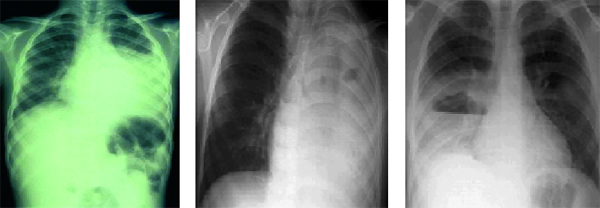

και ιογενούς πνευμονίας (πίνακας 8). Ωστόσο, η τμηματική ή λοβώδης πύκνωση αποτελεί

ισχυρή ένδειξη πνευμονιοκοκκικής πνευμονίας (εικόνα 1), ενώ οι διάμεσες διηθήσεις

συσχετίζονται με ιογενείς λοιμώξεις.

EIKONA 1. Λοβώδης πύκνωση.